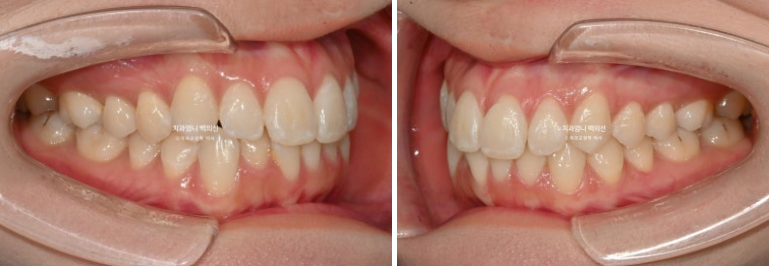

25.01~25.06

중심선은 잘 맞고 과개교합도 좋아졌고 잇몸라인의 개선도 보입니다.

솟아있던 아래 앞니 덧니를 합입시켜 주변치아와 높이를 맞추었고 그 과정에서 잇몸라인도 자연스럽게 높낮이가 개선이 됩니다.